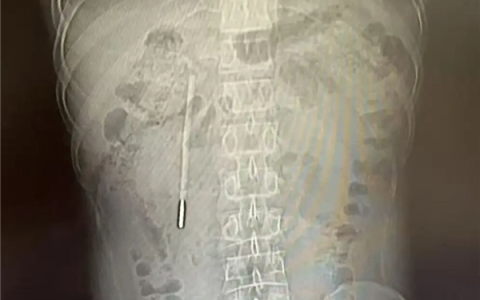

体内待了20年!男子12岁时误吞水银体温计 32岁因腹痛才取出

快科技4月8日消息,据“温医大附一院内镜中心”官方发布,近日,浙江温州32岁的王先生因腹部不适就医。 结果在CT检查中发现其十二指肠内竟藏有一根清晰的异物,经追溯病史这竟然是他20…